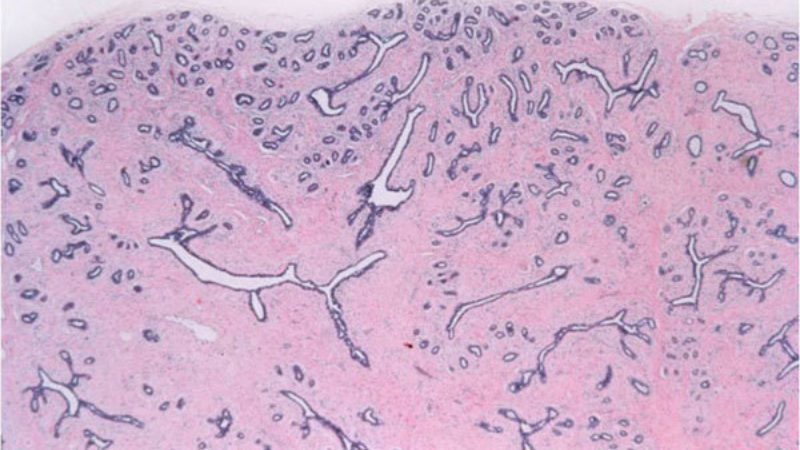

The unit in the breast comprised of the lobules and their associated terminal duct. The breast contains innumerable terminal duct lobular units. All breast carcinomas arise from the epithelial cells in the terminal duct lobular unit.

A normal, benign process that occurs in the breast in which the tissue develops small or large cysts, benign epithelial proliferation, and increased fibrosis. This can cause the breast to feel lumpy or bump. These changes can be painful and typically change during the course of the menstrual cycle.

A benign, fluid-filled space lined with epithelium; cysts can cause a breast to feel lumpy or bumpy.